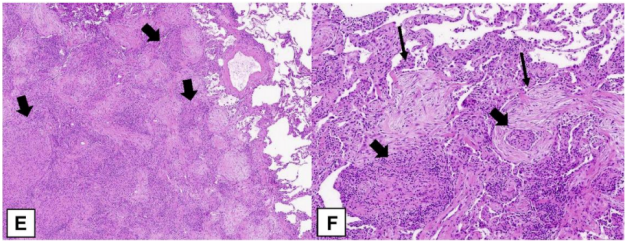

图源:Chest, 2022, 162(1):156-178.从病理方面来讲,OP病变呈斑片状分布;肺泡内、肺泡管见疏松胶原样结缔组织增生,形成Masson小体,主要见于肺泡、肺泡管和终末细支气管;病灶区肺泡间隔有时可见轻微的慢性炎症渗出表现(图19)。

图19 OP的组织病理学

图源:Eur Respir Rev, 2021, 30(161):210094.机化性纤维化包括腔内疏松结缔组织息肉样栓子,突出到远端气腔。肺泡、间隙和肺泡管通常受影响最大,细支气管受影响较小。低倍镜组织学图像(图20A)显示斑片状疏松结缔组织形成的息肉样腔内栓子(粗箭头)区域,突出到远端气道。邻近的肺实质相对正常(细箭头)。图20B示肺泡腔和肺泡管内可见息肉样栓子(粗箭头),但细支气管受累很少(细箭头)。

图20 OP的病理特征

图源:Chest, 2022, 162(1):156-178.